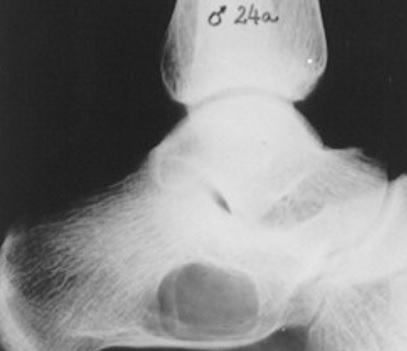

16

Q

Qual diagnóstico?

A

Lesão litica do calcâneo, borda bem delimitada

dx: COS